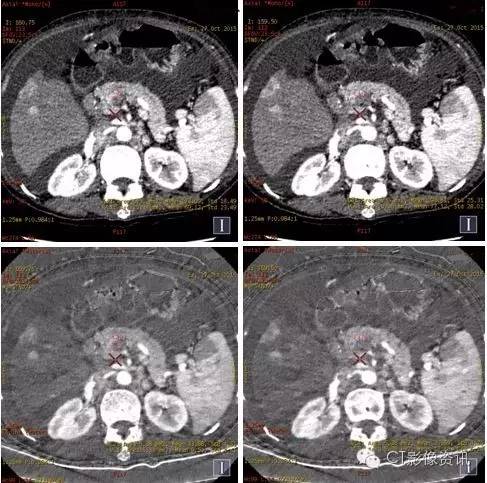

碘基图像对肝脏结节的血供显示更敏感,碘基图上我们可以看到更多清晰的小病灶。

分别测量并计算正常肝脏及病灶在动脉期及门脉期的肝动脉碘分数(注1)及门脉碘含量(注2),结果见下表。

AIF肝脏=5.51/18.53=0.3;PVIC肝脏=18.53-5.51=13.02 AIF病灶=35.65/23.92=1.5;PVIC病灶=23.92-35.65=-11.73

注: 1、肝动脉碘分数AIF(ArterialIodine Fraction)=碘含量(动脉期)/碘含量(门静脉期) 2、门静脉碘含量PVIC(Portal VenousIodine Concentration)=碘含量(门静脉期)-碘含量(动脉期)

癌栓定量分析

动脉期碘基值(9.5~12.88)

栓子定量分析

门静脉期碘基值(31~36)